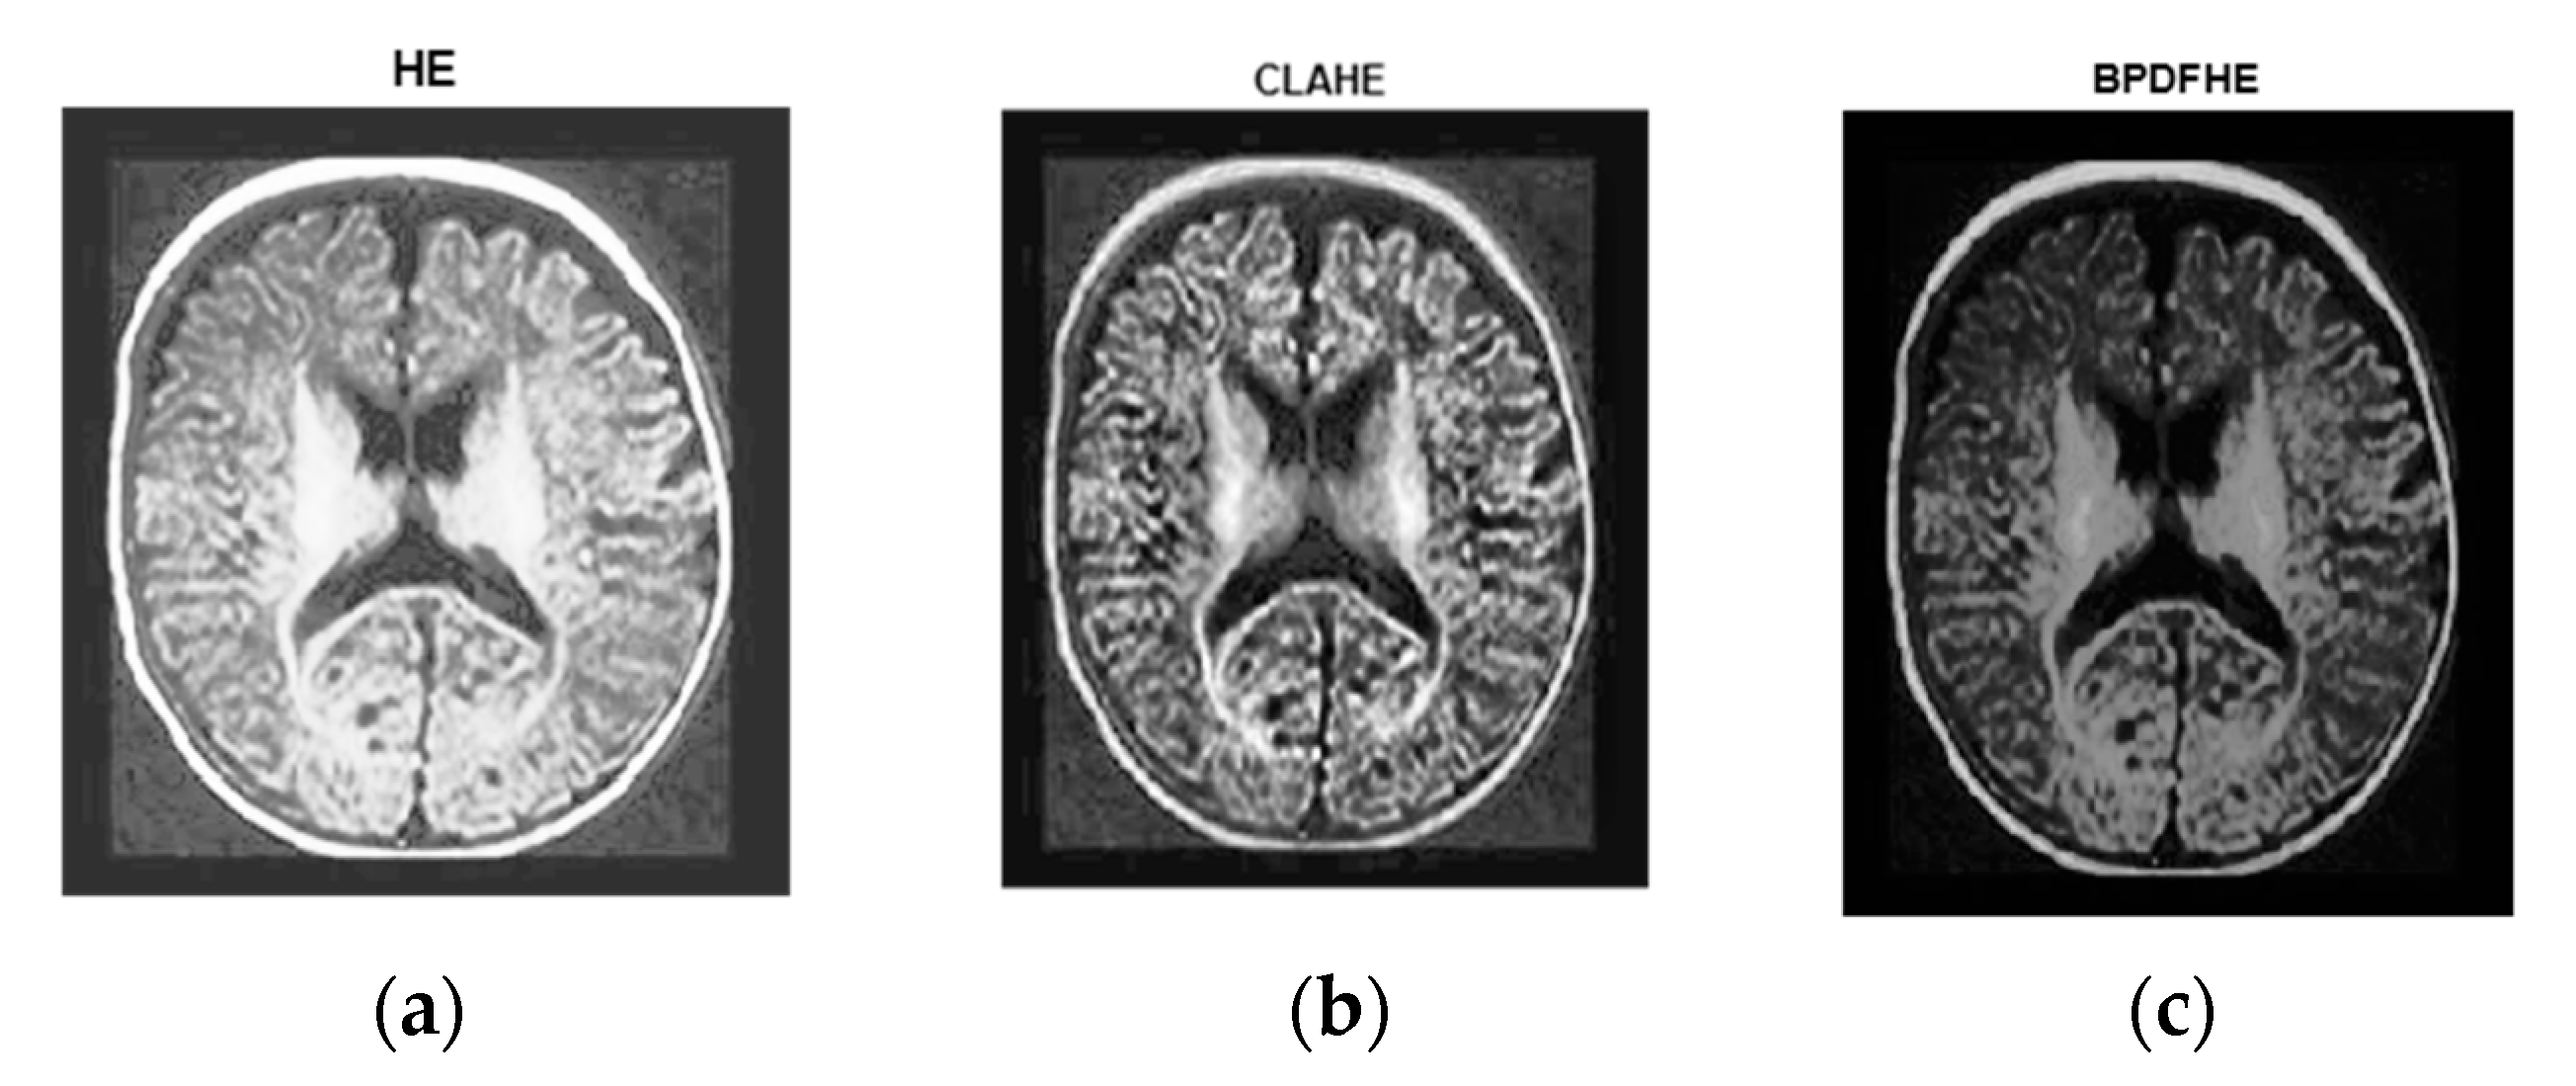

Figure 7a is the original image. Figure 7b is its histogram representation. Figure 8a–c represents the same image enhanced via different preprocessing methods, i.e., HE, CLAHE, BPDFHE, and Figure 9a–c is their respective histograms.

Figure 8.

Preprocessed with (a) HE, (b) CLAHE, and (c) BPDFHE.